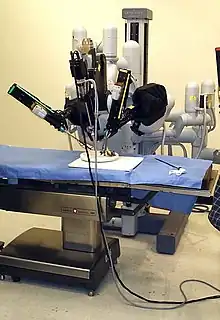

Chirurgie

Elle repose sur la prostatectomie, dite radicale ou totale. Elle consiste en l'ablation de la prostate et des vésicules séminales et peut être précédée d'un prélèvement des ganglions de drainage de la prostate. La chirurgie peut être réalisée par voie ouverte (incision chirurgicale au niveau de l'abdomen ou au niveau du périnée), par voie cœlioscopique abdominale, ou bien à l'aide de l'appareil Da Vinci ; la chirurgie est réservée aux cancers localisés à la prostate et offre de grandes chances de guérison si le cancer est effectivement localisé et peu ou moyennement agressif (agressivité estimée par le score de Gleason) ; elle peut entraîner une incontinence urinaire, le plus souvent temporaire et des troubles de l'érection. Il n'y a pas de supériorité d'une technique par rapport à une autre en ce qui concerne les résultats carcinologiques et les résultats fonctionnels urinaires et sexuels.

Robot médical

Commercialisé depuis 2003, le Da Vinci est un robot médical doté de quatre bras et opéré à distance par un chirurgien. Début 2011, 80 % des prostatectomies réalisées aux États-Unis sont faites à l'aide d'un Da Vinci, contre 20 % en France.